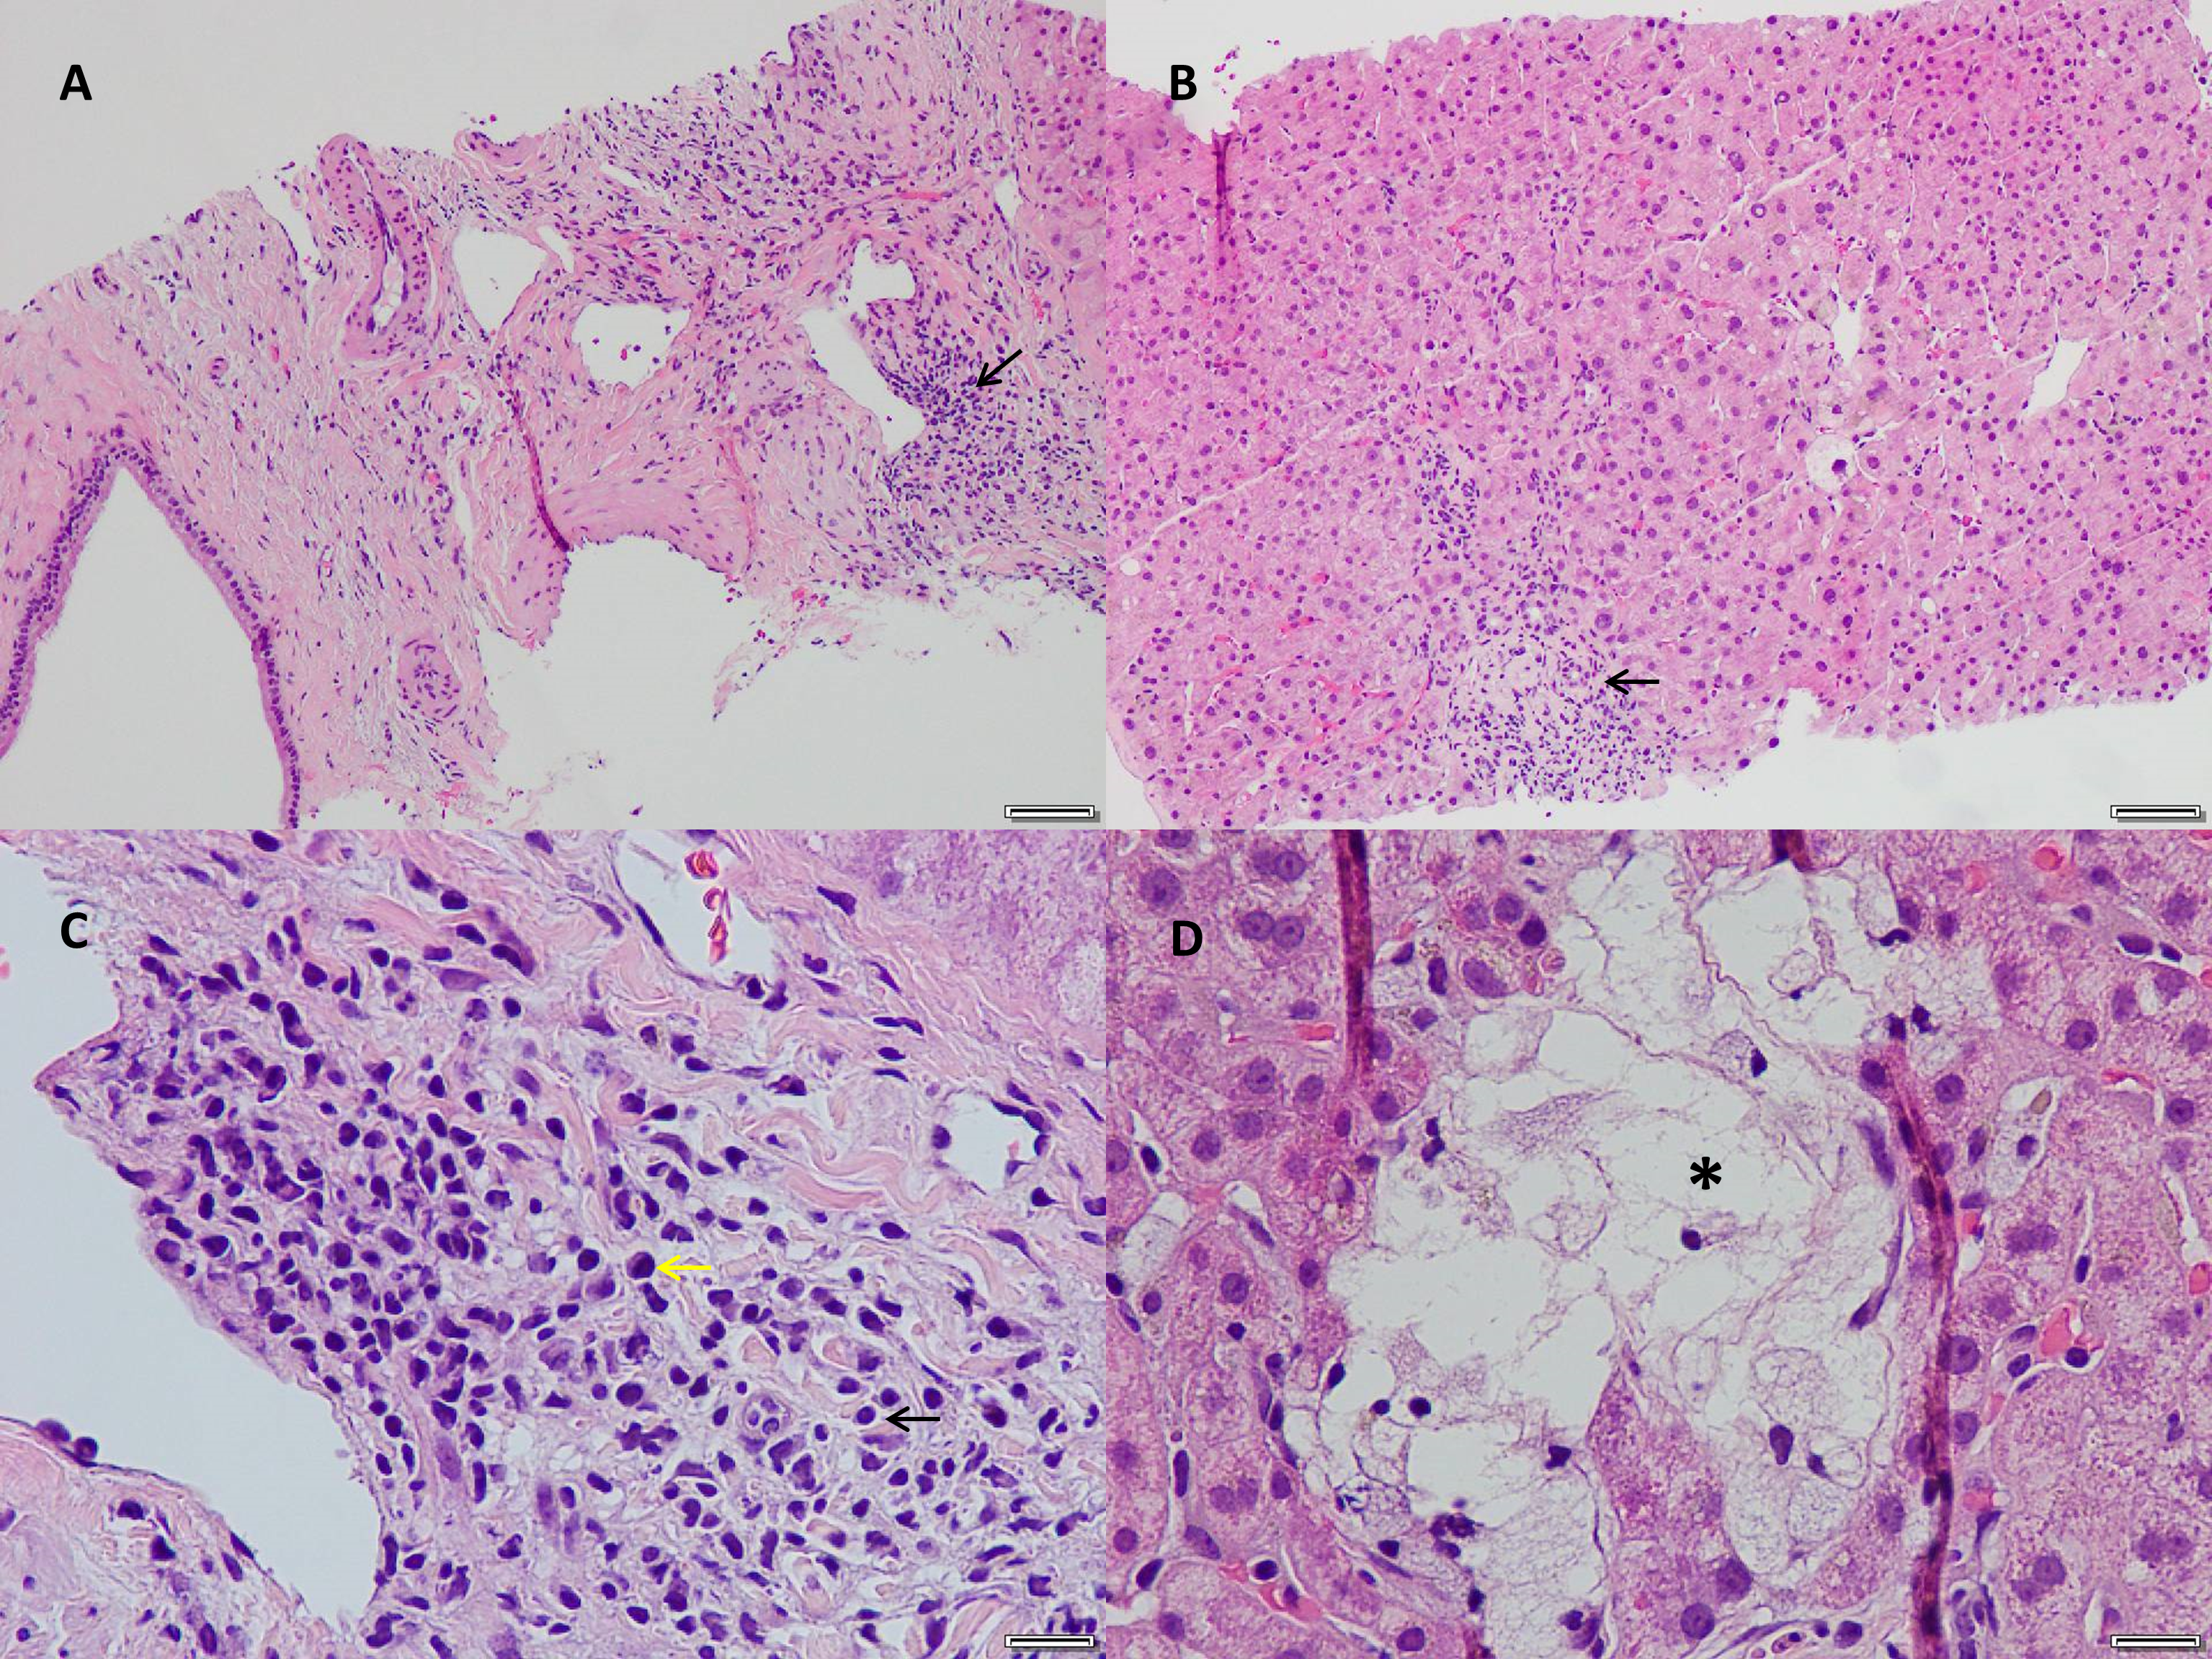

Liver biopsy was performed and it revealed lymphoplasmacytic infiltrate in portal tracts without significant interface activity. Periductal fibrosis with increased IgG4 positive plasma cells (20/hpf) was noted. The majority of the plasma cells were IgG4 and MUM1 positive on the immuno-stains. The other findings were focal lobular lymphoplasmacytic inflammation, hepato-canalicular cholestasis with focal cholate injury, scattered ceroid-laden macrophages, and minimal steatosis. Portal fibrosis was seen on the trichrome stain and minimal (1+) hemosiderosis was seen on the iron stain. CK7 immunostain showed intact interlobular bile duct branches with scattered intermediate liver cells. The copper stain was negative (Figures 1 and 2).

Figure 1: Liver Biopsy. H&E stain. A. Original magnification x 40: Periportal lymphoplasmacytic infiltrate (arrow). B. Original magnification x 100:Lobular inflammation (arrow). C. Original magnification x 200: Inflammation with lymphocytes (black arrow) and plasma cells (yellow arrow). D.Original magnification x 400: Focal cholate injury (asterisks).